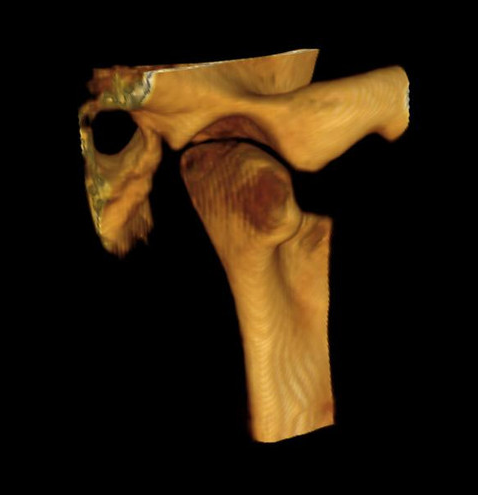

Introducing the CS 9300 Premium Panoramic, Cephalometric, and Cone Beam System from Carestream Dental – your ultimate solution for top-quality dental imaging. This state-of-the-art machine offers both 2D panoramic and cephalometric dental X-rays, as well as adjustable 3D cone beam images in up to seven different field of view sizes, extending up to 17x13.5 cm. This comprehensive range of imaging capabilities makes it a versatile tool, perfect for supporting a wide array of dental, surgical, or orthodontic examinations.

- TMJ (2x and 4x)

3D imaging:

- One-shot cephalometric

- Lateral

- Oblique

- Frontal (AP/PA)

- Submental-vertex

- TMJ disorders